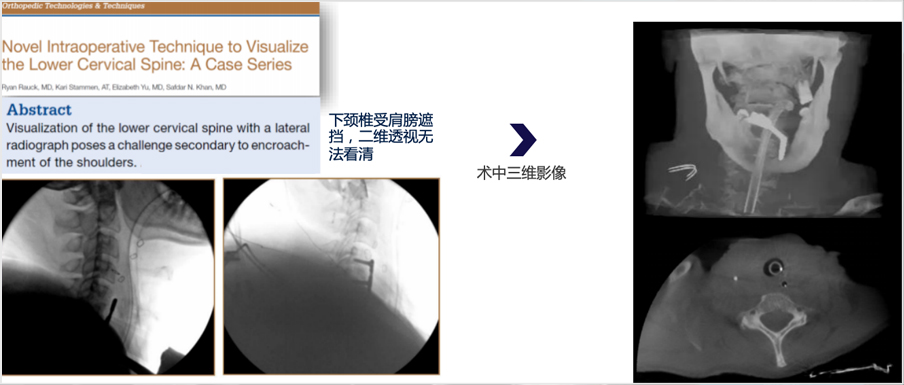

術中二維透視引導存在視野盲區

頸胸交界、復雜脊柱畸形、以及遇到腹內脹氣等情況, 二維圖像無法滿足臨床手術需求

三維影像能大幅提高導航可視化與手術計劃的精準度